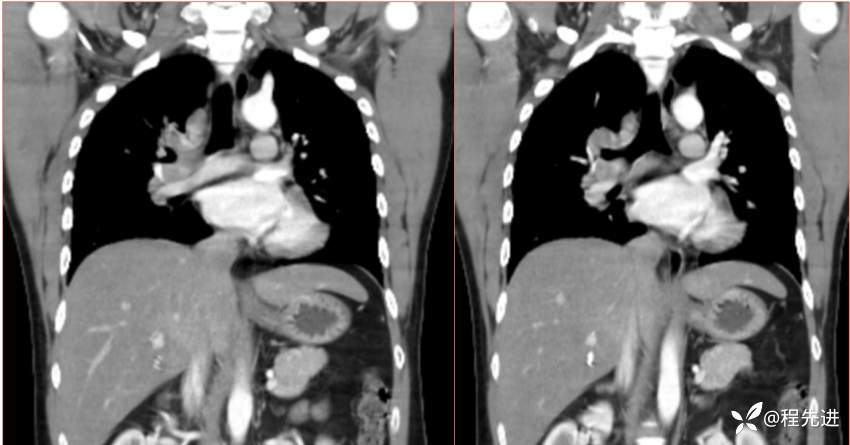

2023国庆特别精彩病例(一)|阵发性刺激性咳嗽,咳少量白色粘液痰1周|结果已公布

患者年龄:34岁

简要病史:患者一周前无明显诱因出现阵发性刺激性咳嗽,咳少量白色粘液痰,咳嗽无明显昼夜节律性,无发热、畏冷、寒战,无头痛、胸闷、胸痛,自行服药后 (具体不详) 症状无缓解,3天前外院胸片检查示右上病变

辅助检查:肺肿瘤标志物:神经元特异性烯醇化酶(NSE):35.72ng/ml(参考值0-16.3);非小细胞肺癌相关抗原211、胚抗原糖类抗原125、铁蛋白、鳞状细胞癌抗原未见异常